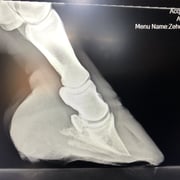

Die Zusammenarbeit von Veterinärtechniker und Tierarzt ist unerlässlich. Röntgenbilder sind absolut notwendig, um die Position des Hufbeines in der Hornkapsel zu erkennen und Sohlen- u. Wandstärke zu beurteilen. Dies ist

maßgebend für die Rehehuf- Korrektur und die Anfertigung des Hufschutzes, einem der Situation angepasster Klebebeschlag. Jeder Rehehuf ist anders, daher gibt es keinen Standardbeschlag. Der Klebebeschlag

• Hufrehebeschlag bei einer 34 Jahre alten Stute

Der Rehe-Huf wurde nach Sichtung der Röntgen Bilder korrigiert und ein reheadaptierter Duplo Beschlag angefertigt. Da das Pferd extreme Schmerzen hatte, wurde es durch den anwesenden Tierarzt sediert. Um dem Tier das Stehen während der Hufbearbeitung zu erleichtern wurde das Team von ANIMAL RESCUE (Dr. Christoph Peterbauer) zugezogen, welches eine unterstützende Hebevergurtung anbrachte.